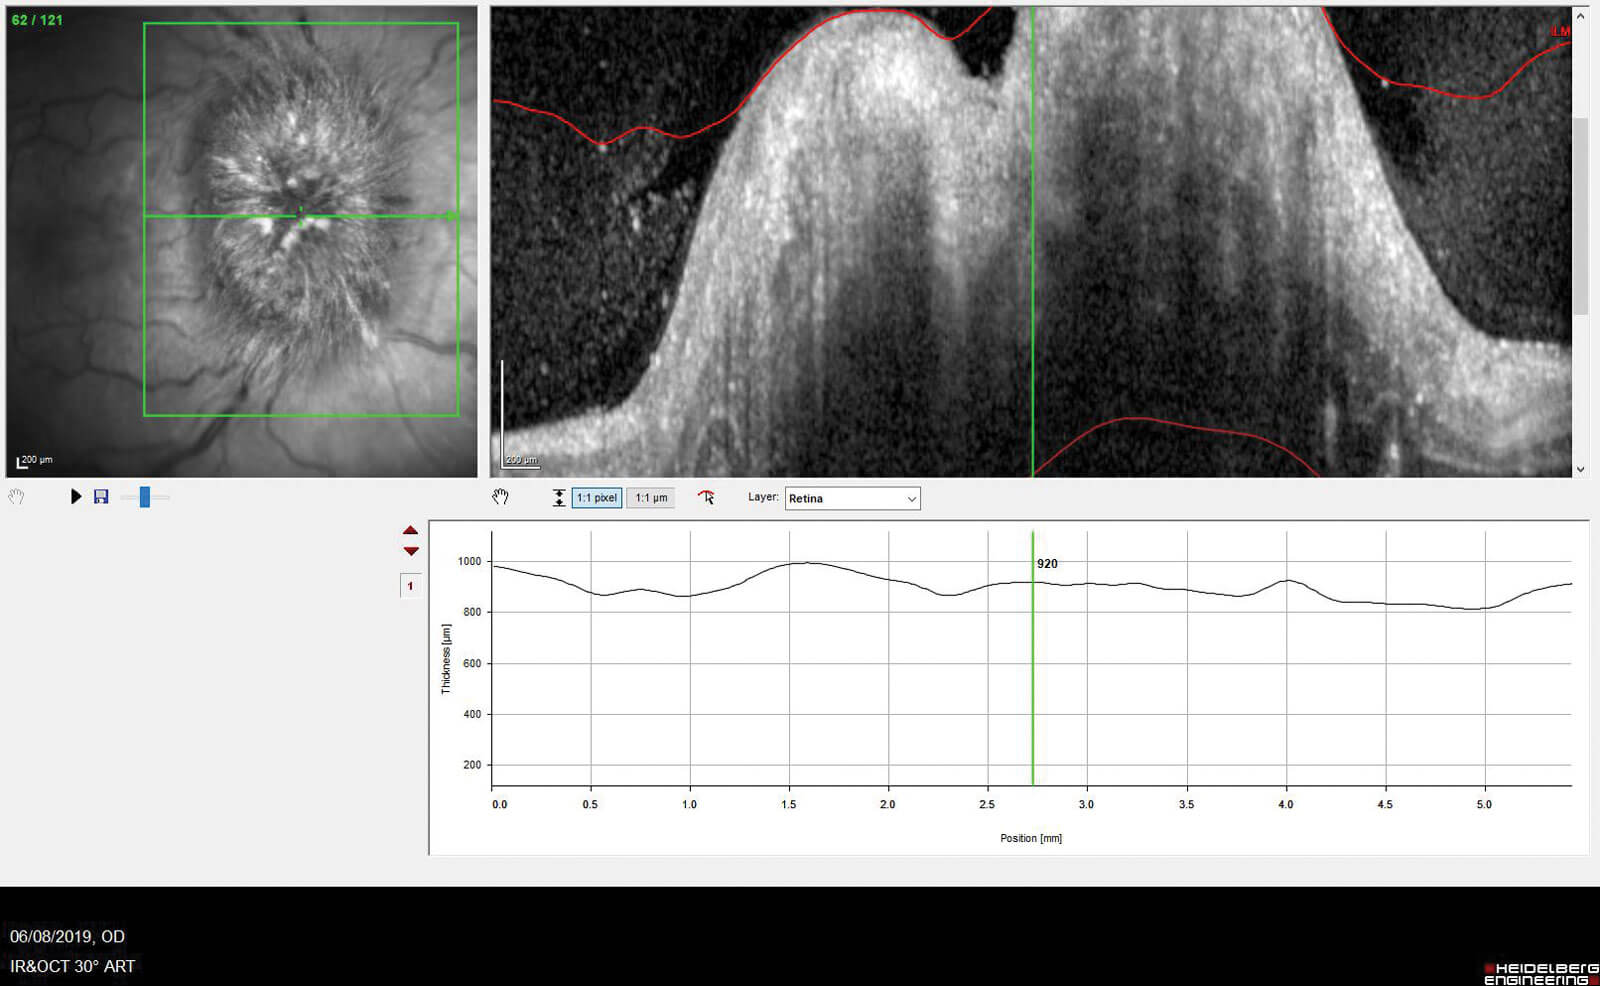

The optic nerve head scan is the second scan which shows us the cross-sectional view of the nerve head. By calculating the distance between the Bruch’s membrane (BM) and inner limiting membrane (ILM) a thickness map is produced, enabling the observation of any swelling and potential causes such as disc drusen. If the disc is more than moderately swollen, then unlike the RNFL scan, we still get a fair view into the optic disc plus an indication of the thickness measurement, though this can still be inaccurate due to inaccurate segmentation, as seen in Figure 2.

Figure 2: ONH scan showing papilloedema in a cross-sectional view.